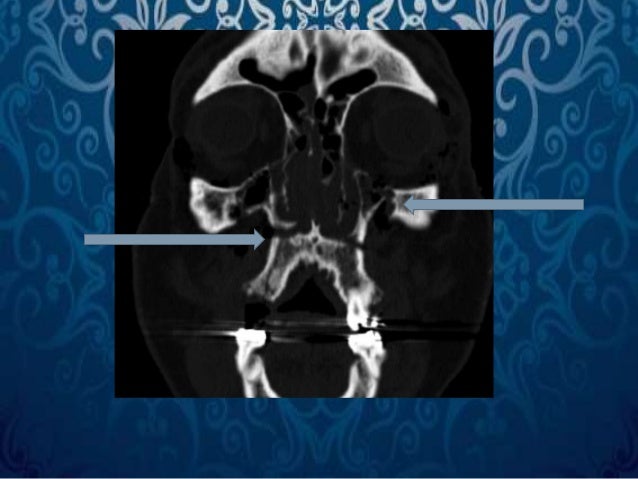

LeFort II fractures extend from one lateral maxillary buttress through the maxilla into the infraorbital rim and nasofrontal junction and are aptly described as pyramidal fractures. Displacement of the maxilla is more likely to be encountered when the fracture extends beyond both the medial and lateral maxillary buttresses. LeFort I fractures are in the horizontal plane inferior to the maxillary sinus and inferior orbital rim, but superior to the teeth ( Figs. Often, fractures extend through the maxillary sinus, as well as the medial and lateral buttresses. They can be unilateral or bilateral, symmetrical or asymmetrical, and are often concomitant with other facial fractures. The initial classification was based on injury patterns caused by low-velocity and low-energy inciting events however now, LeFort fractures are predominately caused by MVAs or other high-energy collisions. This is attributed to the change in injury mechanisms over the past 100 years. Hence, midface fractures often occur in recognizable patterns.įirst described in 1901 by Rene LeFort, LeFort fractures I through III are commonly encountered by the plastic surgeon, but rarely in the pure forms as described by LeFort.

The anatomy of the maxillary and surrounding structures is such that energy is dissipated by fracturing the midface so as to reduce the inertial burden, thus protecting the globe and brain. If any abnormalities are encountered on the exam that may suggest an underlying fracture, craniofacial computed tomography (CT) scans should be ordered and read by the surgeon.įractures of the midface require considerable force and are often caused by MVAs and assaults. Ask the patient to open and close, and then clench the jaw and see if there is any sensation of the bite being “off.” Even the smallest change in occlusion can be readily appreciated by the patient and is more sensitive than the examiner's assessment. Apply downward pressure on the top of the tooth to assess for depression in the socket.Įxamination of the patient's occlusion is vital and should be done in a neutral position. Alternating pressure should be applied to assess for mobility of the tooth. The blunt ends of two instruments should be placed against the facial and lingual aspect of the base of the tooth. The mobility test may be used to assess the stability of the tooth. In cases of acute respiratory failure in which the patient has sustained facial injuries, an aspirated tooth may be the underlying cause. If the tooth was swallowed and passed below the diaphragm, the patient is likely to pass the tooth without incident. To prevent the formation of lung abscesses, aspirated teeth should be endoscopically removed. In the case of neurologic impairment, this may be difficult to ascertain, and radiography of the chest is necessary to evaluate for either swallowed or aspirated teeth. In the case of missing teeth, ask the patient if he or she remembers either losing the tooth, aspirating the tooth, or swallowing the tooth. Each tooth should be assessed for mobility and documentation of broken and/or absent teeth is crucial. An injury to the mucosa may suggest either alveolar or palatal fractures. The oral cavity should be assessed for mucosal lacerations, ecchymosis, and the presence of bone fragments. Ecchymosis, facial edema, subcutaneous hematomas, and epistaxis are often seen in maxillary fractures. If the nasal complex moves along with the maxilla, a LeFort II fracture is likely. If only the maxilla moves, it is likely to be a LeFort I fracture. Assessing the stability of the upper jaw may be achieved by firmly pressing one hand against the patient's forehead and manipulating the maxilla with the other. Both external and internal palpation of the maxilla is necessary. When examining the maxilla, bilateral palpation is often helpful to help assess for step-offs. On physical exam, LeFort fractures are often appreciated as facial distortion and elongation, maxillary mobility, midface instability, and malocclusion.Ī bony examination should follow. A preinjury photograph (state-issued identification cards work well) is often helpful in comparing the patient's preinjury anatomy to postinjury appearance.